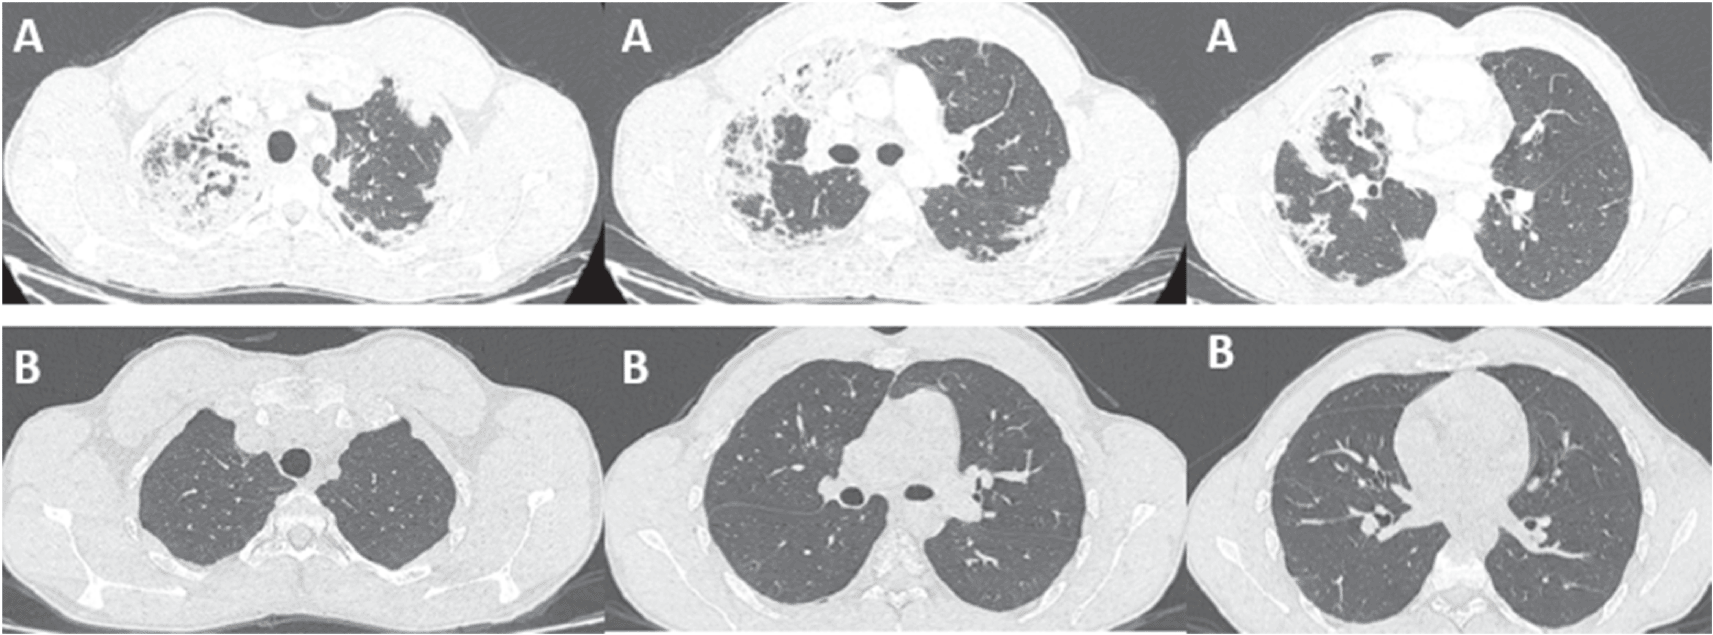

A 21-year-old patient, high-level athlete, was admitted for dry cough and progressively worsening dyspnea for a month. He also reported 10 kg weight loss during this period. He did not have high fever or wheezing. He was a never smoker and he had no previous medical history. Laboratory findings showed an elevated leukocyte count with a high level of eosinophilia (4.57 G/L, 34.7%). Liver and kidney function tests were normal. Chest computed tomography (CT) showed bilateral and peripheral infiltrative shadows, essentially on the right side (Figure 1). Bronchoalveolar lavage fluid (BALF) showed an elevated eosinophil percentage (26%). Antineutrophil cytoplasmic antibodies (ANCA) were negative. FIP1L1-PDGFRA and JAK2 V617F mutations were absent. Video-assisted thoracoscopic lung biopsy showed pulmonary eosinophilia with appearances of organizing pneumonia (Figure 2). The diagnosis of ICEP was established. The patient was managed with high-dose of corticosteroids (20 mg dexamethasone for three days, then 1 mg/kg/day of prednisolone which was tapered over six months). Clinical, biological and radiological improvements were noted. However, the patient relapsed three days after the treatment was stopped. He responded again to steroids. But because of the side effects he experienced from chronic steroid use (muscle wasting, tendon rupture and depression), the decision to initiate an off-label anti-IL5 treatment was made. A monthly 100mg of subcutaneous mepolizumab was started and oral corticosteroids were gradually stopped. With 12 months of hindsight, he was asymptomatic, the eosinophil counts dropped to normal range (Figure 3) with a complete radiological clearance. No adverse reaction to the therapy was noted.

Our second case is a-27-year-old man, active military, admitted for increasing dyspnea, cough and wheezing for a few weeks. He had been diagnosed with asthma one year earlier. He was an ex-smoker of two-five packs per year. Tests showed blood eosinophilia (2G/L, 15%). The C-reactive protein level was 10 mg/L. Chest CT reveled peripheral and diffuse ground glass opacities. The serum Immunoglobulin E level was 502 IU/mL. The BALF showed a marked percentage of eosinophils of 31%. Further investigations were unrevealing for parasitic or fungus infections, vasculitis, and hematologic disorders. Hence, the diagnosis of ICEP was made. Systemic corticosteroids were prescribed (4 days of 20 mg of dexamethasone, then 1 mg/kg/day of prednisone, which was tapered over 3 months). His asthma was treated with daily inhaled budesonide and formoterol. The patient responded well to the therapy: a rapid resolution of symptoms was noted, the eosinophils blood count dropped to normal range, and the pulmonary infiltrates completely disappeared. However, attempts at tapering the corticosteroids below 35 mg were met with three relapses in 16 months, which were associated with clinical worsening, reascension of eosinophil count, recurrence of pulmonary lesions and multiple hospital admissions. A high glucose level due to the chronic steroid use was noted. Subcutaneous mepolizumab 100 mg monthly was initiated. A gradual decrease of oral steroids was well tolerated (Figure 3). The patient is currently at four months of overlap of anti-IL5 and tapering doses of corticosteroids. With a current dose of 20 mg of prednisone, no relapse has occurred.